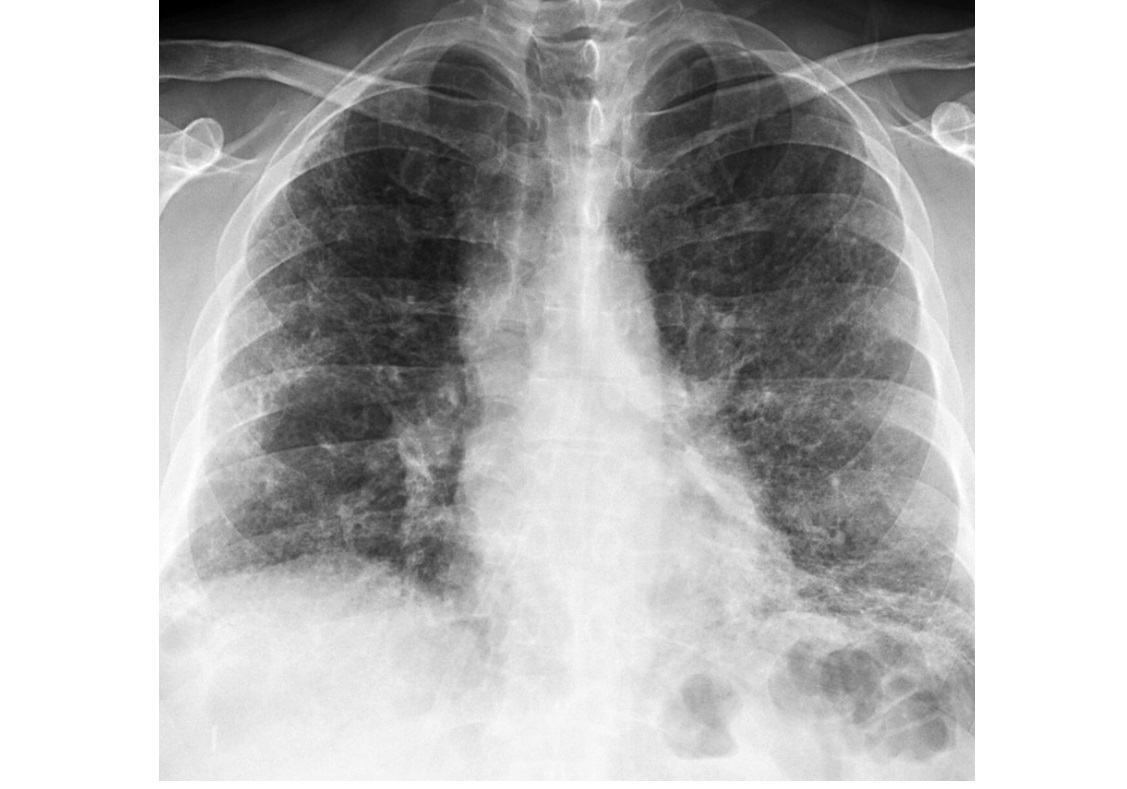

Septic emboli

Peripheral wedges shaped densities +/- cavity

Lower lobe predominant